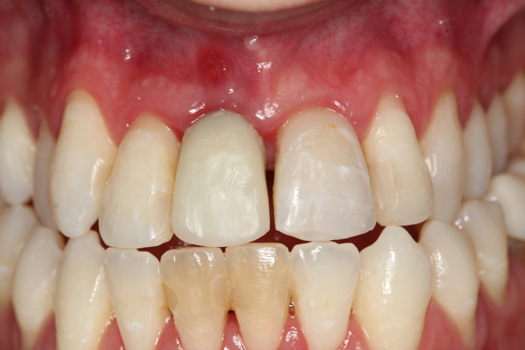

Case 3. TRAUMA: SINGLE Central INCISOR-GUIDED Smile

A 23-year-old man reported to the dental practice on January 3. Apparently, while on vacation and celebrating the New Year, the patient experienced a loss of equilibrium and found himself horizontal in the crosswalk. When surveying the damages, his friends noticed he was missing tooth No. 8. Those who were involved were not able to find the missing maxillary central incisor. The young man was eventually seen about 3 days after the trauma. A CBCT radiograph, study models, and photographs were collected, and teeth Nos. 6 through 10 were immobilized with composite and 20 x 20 orthodontic wire (Figure 14). The CBCT and photos were emailed to the dental laboratory, and the analog intraoral impression with a centric occlusion bite registration was sent via ground transportation. Due to the nature of the trauma, the laboratory and the author expeditiously converted the analog diagnostics and merged all the patient's data sets to develop the plan. Based on the 3D data sets, the laboratory and the dentist were able to accurately assess the volume of bone and soft tissue remaining after the trauma. The volume was still intact and soft tissue was plentiful (Figure 15 and Figure 16).

The decision was to develop a surgical guide, place the implant, and fabricate a screw-retained one-piece non-engaging abutment with a slender emergence profile and a polymethyl methacrylate (PMMA) provisional. Ten days after the trauma, the patient was seen in the dental office for the placement of the dental implant. On the day of surgery, a 3D-printed surgical guide was used, developed from the CBCT radiograph and the digitized impressions (Figure 17 and Figure 18).

The provisional abutment and treatment crown were fabricated in the laboratory with the digital proposals. Platelet-rich fibrin (PRF) clot technology was incorporated to help with soft- and hard-tissue healing (Figure 19 through Figure 21). The screw-retained provisional and the PRF clot were seated immediately after implant placement (Figure 22 and Figure 23). One 4-0 polytetrafluoroethylene suture was placed to maintain papilla. The teeth immobilization splint was placed for 6 weeks (Figure 24). The rationale for splinting teeth Nos. 6 through 10 was due to noticeable plus-2 mobility of the remaining anterior teeth. The provisional implant crown also was included in the splint.

The young man was evaluated at 2 weeks (Figure 25 and Figure 26) and again at 6 weeks (Figure 27). The remaining natural teeth and the implant were stable. The natural teeth had a reduction in mobility to plus 1 at most. The patient's expectation was met. The soft-tissue element of his smile was maintained, and the patient is considering more cosmetic dentistry to optimize his smile. At 16 weeks postoperatively, the radiograph suggested that the digital workflow provided a great benefit to the patient and reduced the amount of chair time in the dental practice, with help from digital technology and the dental laboratory (Figure 28).

Fig 14. Immobilization splint placed 3 days after trauma.

Figure 14

Fig 25. Postoperative periapical radiograph at 2 weeks.

Figure 25

Fig 26. Postoperative at 2 weeks.

Figure 26

Fig 27. Postoperative at 6 weeks.

Figure 27

Fig 28. Postoperative radiograph at 16 weeks.

Figure 28